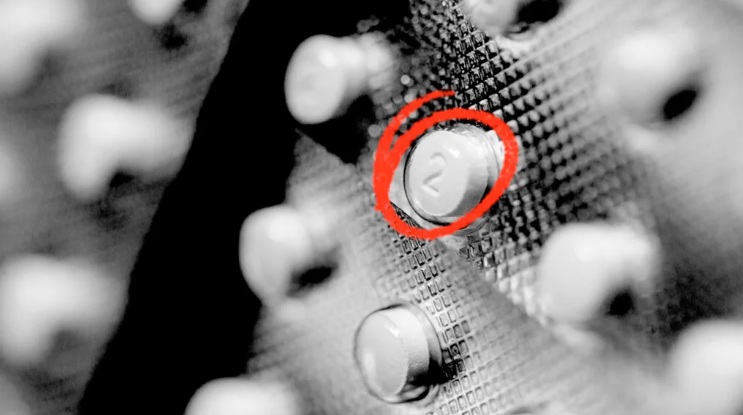

Clenbuterol is a sympathomimetic amine used by sufferers of breathing disorders as a decongestant and bronchodilator. People with chronic breathing disorders such as asthma use this as a bronchodilator to make breathing easier. It is most commonly available as the hydrochloride salt, clenbuterol hydrochloride. Clenbuterol 40mcg for sale Online in Europe.

Clenbuterol is a sympathomimetic amine used by sufferers of breathing disorders as a decongestant and bronchodilator. People with chronic breathing disorders such as asthma use this as a bronchodilator to make breathing easier. It is most commonly available as the hydrochloride salt, clenbuterol hydrochloride. Clenbuterol 40mcg for sale Online in Europe.

Clenbuterol 40mcg, or “clean,” stimulates the heart and central nervous system (CNS). It has the opposite effect as a beta-blocker and a similar effect on the body as epinephrine and amphetamines. How to order Clenbuterol 40mcg online

When people use clenbuterol legally for asthma, the dose is 20 to 40 micrograms dailyTrusted Source.